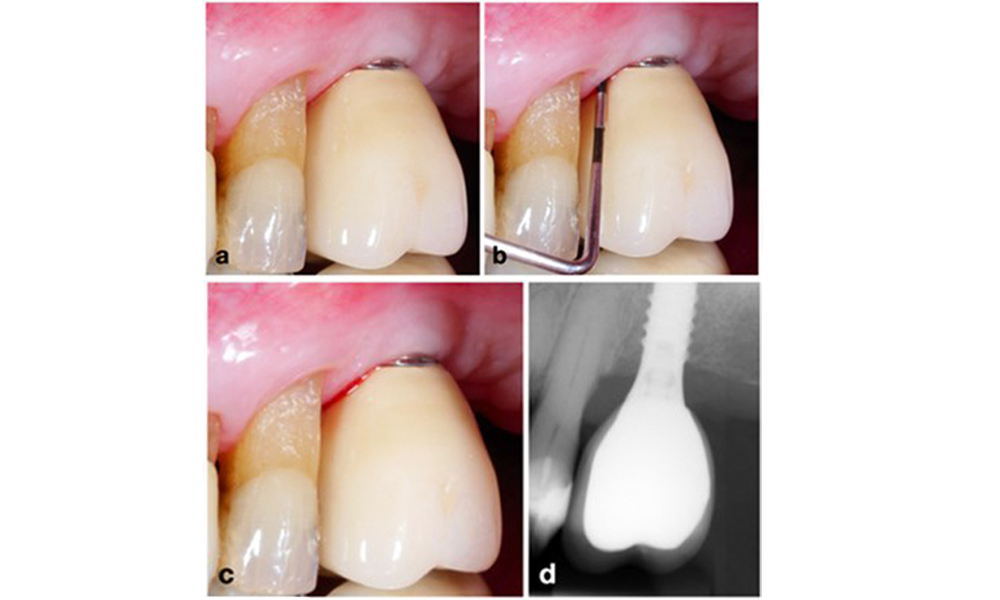

Le World Workshop on the Classification of Periodontal and Peri-Implant Diseases and Conditions de 2017 a établi des critères de diagnostic pour la mucosite péri-implantaire et la péri-implantite (Renvert et al. 2018). La mucosite péri-implantaire est définie comme (1) la présence d'une inflammation autour de l'implant (c'est-à-dire une rougeur, un gonflement, une ligne ou une goutte de saignement dans les 30 secondes suivant le sondage), associée à (2) l'absence de perte osseuse supplémentaire après la cicatrisation initiale (figure 1).

La péri-implantite est identifiée par (1) des signes d'inflammation similaires à la mucosite, (2) des preuves radiographiques de perte osseuse après la cicatrisation initiale et (3) une augmentation de la profondeur de sondage par rapport aux mesures prises peu après la mise en place de la reconstruction prothétique (figure 2). En l'absence de radiographies antérieures, un niveau osseux radiographique de ≥ 3 mm, accompagné d'un saignement au sondage et d'une profondeur de sondage ≥ 6 mm, indique une péri-implantite.

La perte osseuse attendue après la cicatrisation initiale, attribuée au remodelage de l'os marginal, varie en fonction de facteurs tels que le système ou le type d'implant. Par exemple, une perte osseuse de 1 à 2 mm est généralement considérée comme "normale" pour les implants au niveau de l'os avec une connexion externe (figure 2d, implant en position 23).